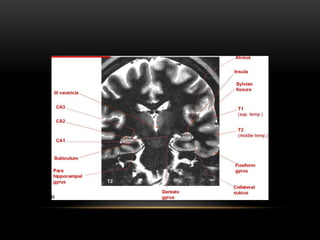

MRI (HIPPOCAMPUS)

• Club-shaped structure divided into three

parts: head, body, and tail.

• In coronal plane form an S-shaped

configuration.

• Consists of two interlocking C-shaped

structures: the cornu ammonis and the

dentate gyrus.

• Gray matter of the hippocampus is an

extension of the subiculum of the

parahippocampal gyrus.

Primary signs-

Reduced hippocampal volume : hippocampal

atrophy

Increased T2 signal

Abnormal morphology : loss of internal

architecture (interdigitations of hippocampus)